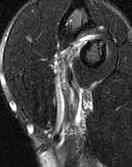

DB 1DB 2

Coronal MRI with 2 cm retracted distal biceps tendon